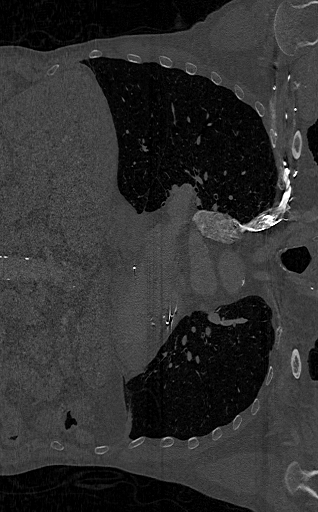

Просмотрите 2D срезы с помощью imshow функция.

figure imshow(XY,[],'Border','tight');

imshow(XZ,[],'Border','tight');